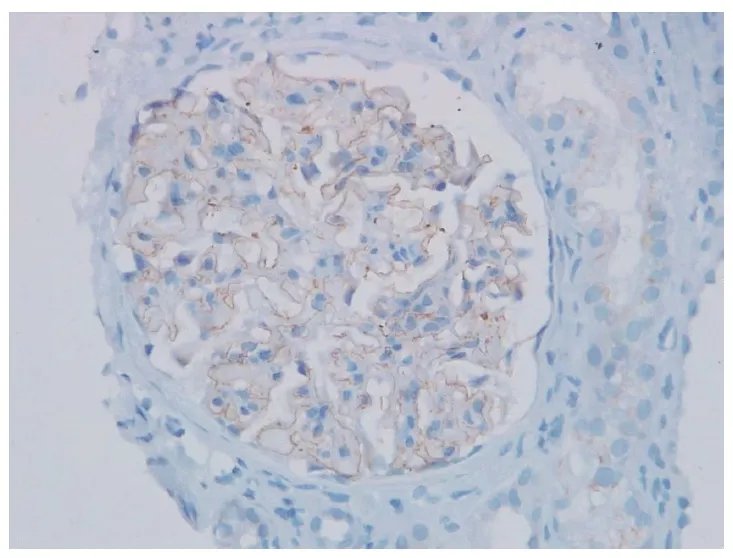

A biópsia renal foi compatível com nefropatia membranosa, além disso, foi identificado marcação na membrana basal glomerular para NELL1 (imuno-histoquímica para NELL1, 400×).